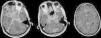

Caso clínicoVarón de 38 años de edad, cocainómano, comienza con cefalea y disminución de la agudeza visual bilateral, interpretado como neuritis óptica, recibió tratamiento con corticoides. Evolucionó con hipoacusia derecha, cuadriparesia nivel T3 y trastornos vesicales. Se realizó RM de cerebro y columna completa con contraste observándose compromiso leptomeníngeo difuso multinodular e imagen seudoquística interhemisférica, asociado a lesiones expansivas intramedulares cérvico-torácicas (figs. 1 y 2). Se estudió con punción lumbar (presión de apertura de 100cmH2O, acelular, glucorraquia normal y proteinorraquia de 107mg/dl), cultivo para gérmenes comunes, micobacterias y hongos, PCR para HSV1-2, VVZ, CMV, VEB y TBC negativos, VDRL en LCR, serología para HIV, micoplasma y toxoplasma negativos. Perfil reumatológico y ECA, sin hallazgos. Inició tratamiento empírico contra toxoplasma y TBC, sin respuesta. Luego de 18 meses de evolución, se realizó biopsia meníngea, arribándose al diagnóstico de pPNET-SNC con t(11;22) (q24;q12). Debido a lo avanzada de su enfermedad, se decidió continuar con medidas paliativas.

RM de cerebro. Secuencia axial T1 volumétrico con contraste. Extenso engrosamiento y realce leptomeníngeo de aspecto nodular de distribución basal, perimesencefálica y adyacente a los senos cavernosos, con extensión a cisternas peritroncales y magna. Formación seudoquística en la cisterna interhemisférica con realce periférico y mínimo efecto de masa.